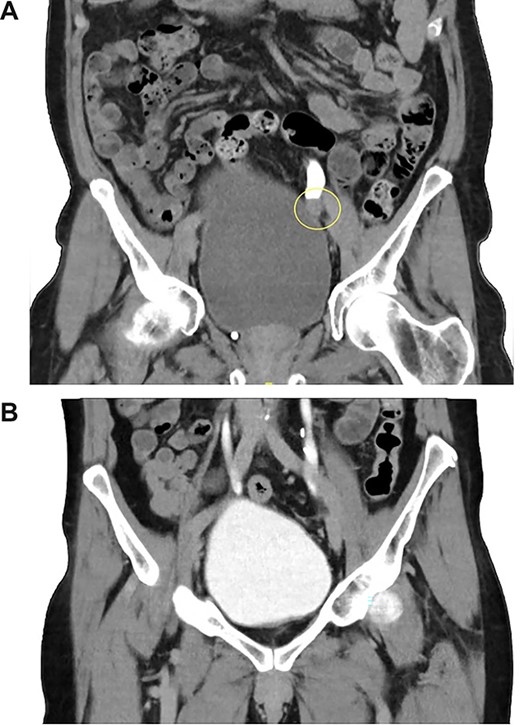

Computed tomography-intravenous pyelogram (CT-IVP) revealed a 1.7-cm intraluminal mass within the left distal ureter that extends beyond the ureteric lumen into peri-ureteric fat, with moderate left hydroureteronephrosis (Fig. 1A).

(A, B) CT-IVP before the surgical excision and 6-month post-operation.

The patient recovered well post-operatively and was discharged home after removal of drain tubes and catheter. Repeat CT-IVP 5 months post-operation showed no evidence of tumor recurrence (Fig. 1B).